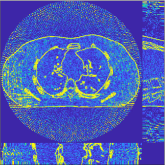

This section compares the reconstruction quality and runtime among the proposed MBIR method, PWLS-ST-, and other three MBIR methods, PWLS-EP, PWLS-DL, and PWLS-ST-. Table I shows that, for both 2D and 3D sparse-view CT reconstructions of the XCAT phantom, the proposed PWLS-ST- model outperforms PWLS-EP and PWLS-ST- in terms of RMSE. In addition, PWLS-ST- using a square transform (of size ) achieves lower RMSE than PWLS-DL using an overcomplete dictionary (of size ) for 2D sparse-view reconstructions. Fig. 3(a) and Fig. 4 show the reconstructed images for 2D and 3D phantom experiments, with different reconstruction models and different number of views. (See the corresponding error maps in the supplement.) The proposed PWLS-ST- consistently gives more accurate image reconstructions compared to other MBIR methods. Specifically, PWLS-ST- has smaller errors in the heart region (see zoom-ins in Fig. 3(a)) of 2D reconstructions than PWLS-DL and PWLS-ST-. In addition, compared to PWLS-ST-, PWLS-DL and PWLS-ST- have some ringing artifacts around the edges with high transition, e.g., edges between air and soft tissues. (See a comparison of profiles of PWLS-ST- and PWLS-ST- in the supplement.) In particular, PWLS-ST- and PWLS-DL give more visible ringing artifacts for 2D reconstruction from fewer views, and PWLS-ST- has these ringing artifacts for 3D reconstructions regardless of the number of views (see zoom-ins in Fig. 4). Table II reports runtimes of different MBIR methods in reconstructing the -views XCAT phantom scan. (FBPConvNet is a non-MBIR method and its runtime for processing a image is approximately one second with a TITAN Xp GPU.) While providing better reconstruction quality, the proposed Algorithm 1 of PWLS-ST- has shorter runtime compared to the algorithms of PWLS-DL and PWLS-ST- in Section III-A. Similar to the PWLS-EP algorithm, the reconstruction time of the PWLS-DL, PWLS-ST-, and PWLS-ST- algorithms can be further reduced by using ordered subsets [51].

![]() |

| (a) 2D fan-beam CT experiments |

| (b) 3D axial cone-beam CT experiments |